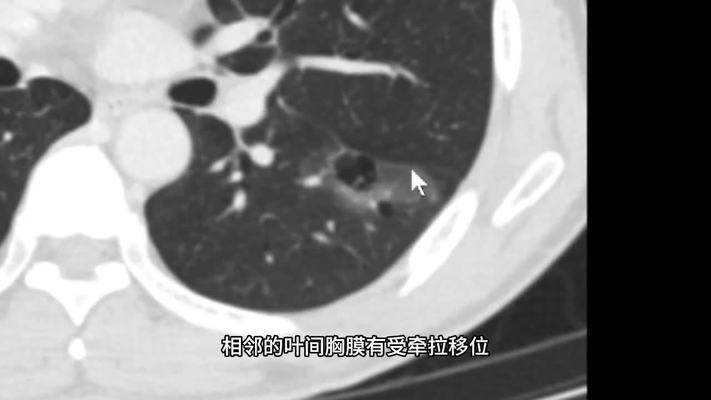

500例有结果的肺结节CT分享第187例,混合型磨玻璃肺肿块 网易公开课

500例有结果的肺结节CT分享第187例,混合型磨玻璃肺肿块。听TED演讲,看国内、国际名校好课,就在网易公开课 登录/注册 已购课程个人中心 已购课程优惠券我的收藏播放记录我的证书墙内容中...